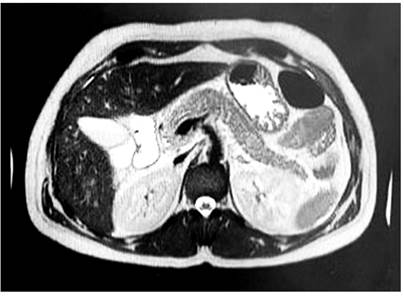

Se realizó una ecografía biliar que descartó colelitiasis y coledocolitiasis, aunque hubo evidencia de inflamación pancreática. Una tomografía axial computarizada (TAC) abdominal contrastada mostró necrosis en el cuerpo del páncreas sin identificar colecciones definidas, compatible con pancreatitis aguda necrotizante (Balthazar C) (Figura 2) y una colangiorresonancia mostró que la paciente tenía pancreatitis aguda edematosa intersticial con una colección peripancreática de 32 x 23 mm (Figura 3), la cual se clasificó como moderada, según el índice de gravedad clínica, con un APACHE II (Acute Physiology and Chronic Health Evaluation II) de 6 puntos, y una valoración de 1 punto en la clasificación modificada de Marshall.

En este caso, el diagnóstico se realizó por exclusión. Se solicitó una ecografía abdominal que descartó etiología biliar; la TAC abdominal contrastada fue la segunda elección, esta mostró la presencia de pancreatitis necrotizante y una posible colección que fue aclarada mediante una colangiorresonancia.

La ecografía hepatobiliar es un método útil para el diagnóstico inicial; sin embargo, presenta una sensibilidad del 25 %-86 % para identificar la AHP y disminuye en cuadros de pancreatitis9. La TAC abdominal contrastada es el estándar de oro imagenológico para determinar el grado de gravedad de la pancreatitis e identificar complicaciones pancreáticas y extrapancreáticas, así como colecciones. La resonancia magnética (RM) es el estudio alternativo en caso de contraindicación o incertidumbre al diagnóstico1.